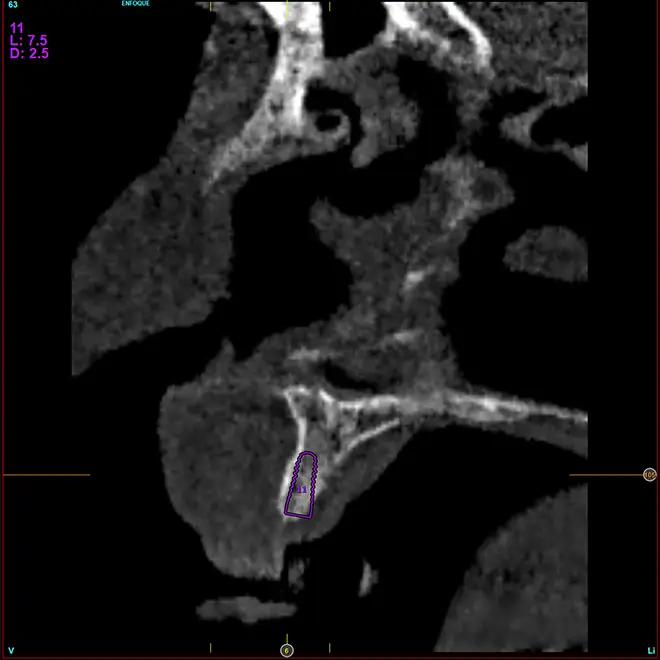

En la zona correspondiente a la pieza 24, tenemos una atrofia extrema también pero en este caso en sentido vertical, con una cresta residual de 3,1 mm de grosor, como podemos ver en el corte seccional del cone-beam (fig. 11). En este caso se planifica la colocación de un implante de 2,5 mm de diámetro y 6,5 mm de longitud (con plataforma reducida de 3 mm -plataforma 3.0, biotechnology institute-) (fig. 12). Igualmente, en la zona anterior de la premaxila, tenemos una situación muy similar donde el volumen óseo es reducido, incluso más que en la zona del segundo cuadrante y, por ello, optamos también por implantes de 2,5 mm de anchura y plataforma de 3 mm (figs. 13-16).

Fig. 11. Corte de planificación de la zona correspondiente a la pieza 24, que presenta una atrofia ósea en anchura extrema con 3,1 mm de anchura residual.

Fig. 12. Planificación del implante de 2,5 mm de diámetro y 6,5 mm de longitud que será colocado en la zona.

Figs. 13-16. Imágenes del cone-beam del área de la premaxila con una anchura ósea muy disminuida y la planificación de implantes de 2,5 mm de diámetro y 3 mm de plataforma.